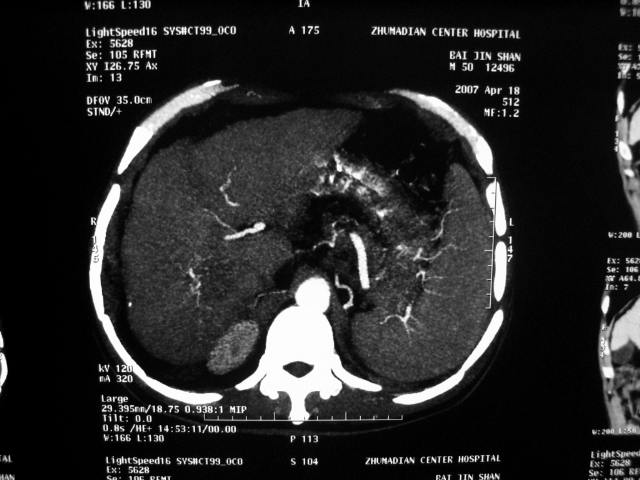

标题: CT7751:病人,50岁,肝硬化多年,行CT三期扫描 [打印本页]

标题: CT7751:病人,50岁,肝硬化多年,行CT三期扫描

增强扫描所传图像不全面,应传各期图像,单传动脉期不能完全说明问题。

肝硬化 脾大 胃底静脉曲张 肝癌 门腔间淋巴结肿大

肝癌、肝硬化、脾大、门静脉高压、胃底静脉曲张.

肝硬化、脾大,静脉曲张,肝右叶低密度灶,增强无明显强化,还是考虑肝癌可能性大,建议结合afp检查。